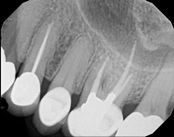

Missed canals and sclerotic orifices/canals:

Before

4-month post-opIn this situation, some would say the canals are so “calcified” that root canal treatment can’t be done; or sometimes the canal can’t be found. And because of that the tooth would need an extraction and an implant. In some instances, root canal therapy can’t be done but that does not mean the tooth is a loss. The solution is micro-apical surgery, an apicoectomy.